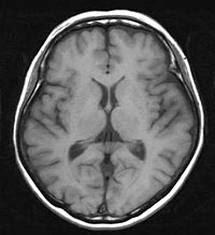

マア 脳MRI, 脳血管、脳MRA 全て問題なしでした♪